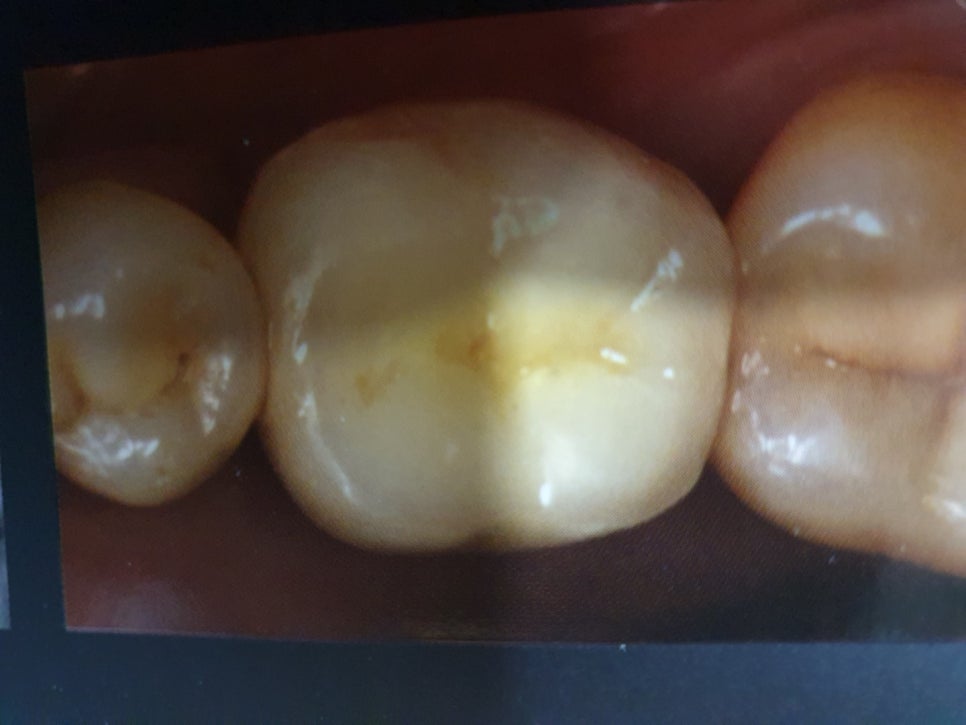

2차 수술을 마치고 2주 정도가 지나서 예후가 좋으면 아래사진과 같이

치아를 만들어서 끼우게 됩니다.

치아를 만들때 금이나 PFM, 지르코니아등의 재료로 최종 보철물을 만들게 되는데

최종 보철물의 재료에 따라 임플란트 금액의 차이가 나게 됩니다.

가장 저렴한 것이 치아 안쪽은 메탈로 하고 겉은 치아색으로 만드는 PFM이며

금이나 지르코니아로 만들경우는 PFM보다 20만원정도 더 비용부담이 있습니다.

금은 인체친화적인 재료라 이물감이 가장적은 반면에 금고유의 색상으로 인해 심미적인 면에서는 많이 떨어지지만

연세가 좀 있으신 어르신들의 경우는 금을 선호하시는 경향이 있습니다.

지르코니아는 아주 단단한 재료이며 자신의 치아색과 동일한 색으로 맞출수가 있어 본인도 겉만봐서는임플란트치아인지자연치인지구분하기힘들정도로 심미적으로아주뛰어납니다.

젊은층에서는당연히선택하는 것으로

많이 선호하지만 금보다는 단단해서 약간의 교합을 잘 맞추는 것이 아주 중요합니다.

신논현역치과 임플란트잘하는 스마일뷰에서 어금니임플란트를완성한모습입니다